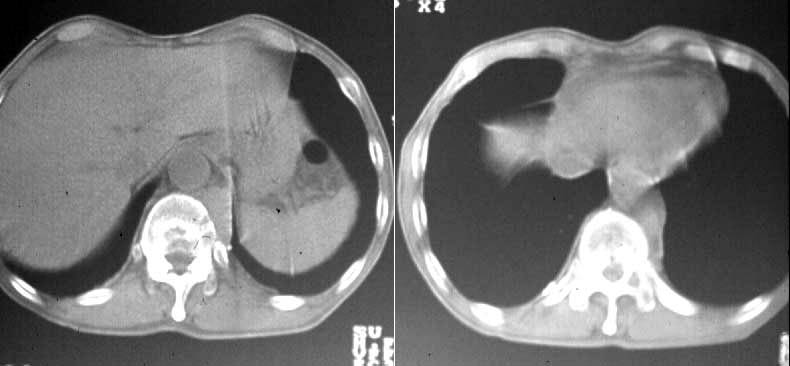

(2)compartment解析に関しては代表的なものは、1-compartment model(秀毛らの非線形model(Fig.3)に始まるが、篠原が報告した如く線形modelでの短時間に演算可能な方法でも実用的であった。Veraらが唱えた3-compartment modelは採血を伴うmodel式を利用しており、やや煩雑さを伴っている。河らが提唱した5-compartment modelは複雑な計算式を必要としているが、肝最大除去率(Rmax)を算出可能である。(Fig.4)病的 hotなし。 | 第12胸椎に骨溶解像。 | 第12胸椎に 低信号域。 |